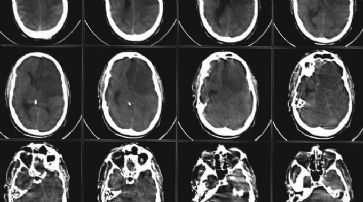

Glasgow - Fünf durch ihren Schlaganfall schwer beeinträchtigte Patienten haben nach der Injektion von Stammzellen ins Gehirn erste kleine Anzeichen einer Besserung ihres gesundheitlichen Zustandes gezeigt.

Der behandelnde Mediziner Keith Muir von der University of Glasgow zeigte sich von den leichten bis moderaten Verbesserungen «überrascht». Der Wissenschaftler betont, dass es noch zu früh ist, um zu sagen, ob diese Veränderung des Zustandes auf die erhaltene Behandlung zurückzuführen ist. Die Ergebnisse werden auf der ab 29. Mai in London stattfindenden European Stroke Conference der Öffentlichkeit vorgestellt.

Die Patienten nehmen an einer kleinen klinischen Studie mit insgesamt neun Teilnehmern in einem Alter von 60 Jahren bis über 80 Jahren teil. Ziel ist es, am Southern General Hospital in Glasgow festzustellen, ob dieses Verfahren zur Behandlung von Schlaganfällen sicher ist. Dabei werden Stammzellen in die geschädigten Bereiche des Gehirns injiziert. Es handelt sich dabei um einen der weltweit ersten Tests für den Einsatz von Stammzellen bei Patienten. Die Ergebnisse zeigen, dass es bisher keine nachteiligen Auswirkungen für die Patienten gegeben hat. Derzeit ist jedoch nicht feststellbar, ob die Verbesserungen auf die intensive medizinische Betreuung der Patienten zurückzuführen sind. Es ist gut belegt, dass das Wohlbefinden, das aus dieser Aufmerksamkeit resultiert, positive Auswirkungen auf die Gesundheit von Menschen haben kann. Die Experten gehen davon aus, dass es bei Patienten nach den ersten sechs Monaten nach dem Schlaganfall eher zu keinen Verbesserungen kommt. Bei allen Teilnehmern lag der Schlaganfall jedoch zwischen sechs Monaten und fünf Jahren zurück.

Stammzellen werden die geschädigten Bereiche des Gehirns injiziert. /

Dass sich der Zustand von einem der Teilnehmer oder sogar von fünf Patienten verbessert, war laut Muir nicht zu erwarten. Der Mediziner erklärt, dass es merkwürdig wäre, handle es sich dabei lediglich um einen Zufall oder einen Placebo-Effekt. «Wir haben Menschen erlebt, die jetzt nach Jahren völliger Bewegungsunfähigkeit ihre Finger bewegen können. Wir haben Menschen gesehen, die sich erstmals wieder alleine in ihrem Haus bewegen können und haben beobachtet, dass Menschen erstmals auch wieder ihre Umgebung wahrnehmen», so Muir.